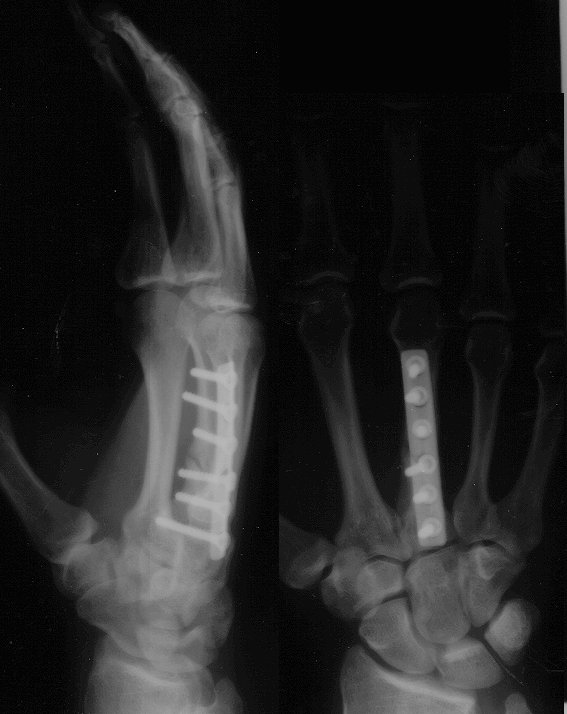

See the results of my

horse accident (Warning!

x-ray picture)